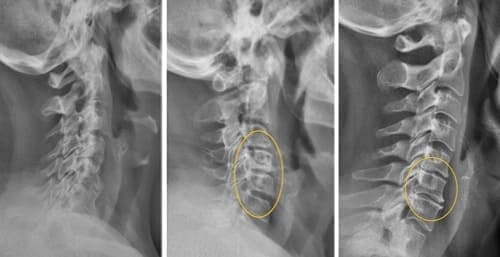

Uma das poucas soluções que a ciência médica pode oferecer é uma cirurgia complexa e arriscada para remover a hérnia e colocar pinos metálicos. Mas pense bem! Mesmo os melhores cirurgiões reconhecem que a cirurgia da coluna vertebral é uma medida extremamente imprudente e perigosa, que muitas vezes leva a problemas mais graves, infecções, complicações e até mesmo à morte.

A remoção da hérnia da coluna vertebral com pinos metálicos é um procedimento que muitas vezes pode causar inúmeras complicações: o risco de infecção, amputação ou sépsis aumenta em 60%. O processo de recuperação é longo e doloroso, com um risco significativo de incapacidade.

É importante notar que, em dois terços dos casos, a hérnia regressa dentro de quatro anos após a remoção, uma vez que a causa não foi eliminada!